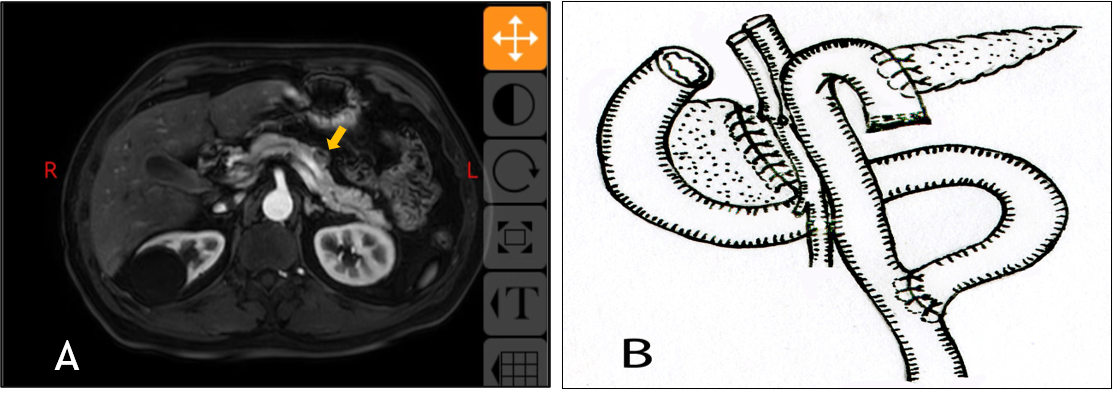

图A术前上腹部增强MRI提示胰腺导管内乳头状粘液瘤(IPMN)

图B胰腺近切端缝合,远切端空肠Roux-en-Y吻合(示意图)